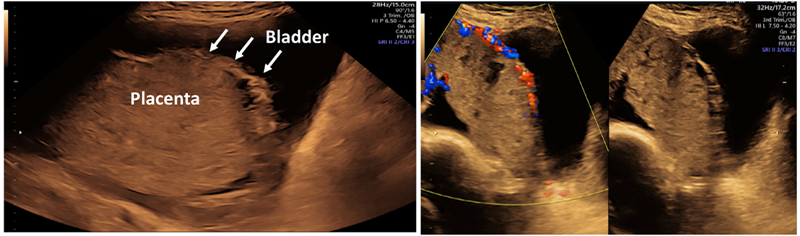

이전 제왕절개술 등 자궁절개술을 받은 임신부에서 전치태반이 관찰되면 반드시 태반유착에 대한 자세한 평가를 하여야 합니다(그림1). 또한 ISUOG에서는 자궁절개수술력이 있는 임신부의 전치태반은 모두 잠재적인 중증 태반유착으로 간주하고, 초음파소견과 무관하게 이에 대한 처치가 가능한 기관으로 산모를 전원하도록 권유하고 있습니다(Good practice point). 자궁근종절제술 및 자궁뒷벽 절개 등 흔하지 않은 수술 부위에 태반이 위치하여 초음파 확인이 어렵거나, 심한 태반유착과 함께parametrial invasion이 의심되는 등 초음파검사로 태반유착의 평가가 어려울 경우 반드시 MRI검사로 태반유착을 확인하도록 권고하고 있습니다.

그림 1. Placenta accreta spectrum. 방광벽에 인접한 태반(왼쪽)과 불규칙한 uterovesical interface 및 placenta lacunae가 관찰(오른쪽). from ISUOG practice guidelines